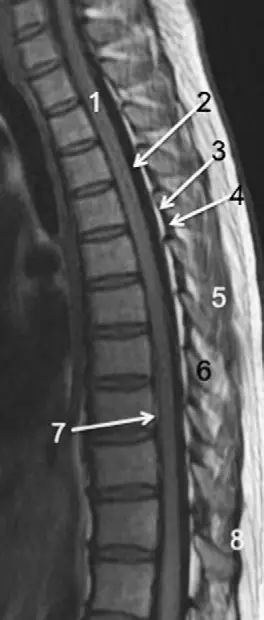

图1正常脊椎的MRI检查,左图为正中矢状位T2WI,右图为T1WI图 2 胸椎 T2WI 轴位图:1,肋椎关节;2,类骨头;3,黄韧带;4,椎弓根;5,椎弓板;6,横突;7,棘突;8,肋横突关节;9,肋结节;10,半奇静脉;11,后纵韧带图 3 腰椎矢状位 T1WI 序列成像:1,脊髓;2,脊髓圆锥;3,马尾;4,蛛网膜下腔;5,硬膜外脂肪;6,黄韧带;7,棘间韧带;8,棘上韧带;9,椎体静脉丛;10,硬膜外静脉丛;11,硬膜外脂肪;12 主动脉图 4 L5/S1 水平轴位 T1WI 序列成像:1,腰肌;2,L5 神经根(前支);3,L5 神经根(后支);4,黄韧带;5,蛛网膜下腔;6,马尾神经根;7,小关节面;8,髂腰韧带;9,左髂外静脉;10,左髂外动脉;11,右髂外动脉;12,右髂外静脉;13,多裂肌;14,竖脊肌组图 5 腰椎旁矢状位 T1WI 序列成像:1,腰静脉;2,腰动脉;3,椎间孔静脉;4,脊神经节后根;5,椎间孔静脉;6,关节面;7,多裂肌;8,竖脊肌群;9,胸腰筋膜,后层图 6 胸椎 T1WI 序列成像:1,胸髓;2,蛛网膜下腔;3,硬膜外脂肪;4,黄韧带;5,多裂肌;6,棘突;7,硬膜外静脉;8,棘上韧带图 7 胸椎矢状位 T2WI 序列成像:1,胸髓;2,蛛网膜下腔;3,黄韧带;4,多裂肌;5,棘突;6,棘上韧带;7,椎体静脉;8,脊髓圆锥;9,马尾图 8 胸椎旁矢状位 T2WI 序列成像:1,硬膜囊后壁;2,硬膜外脂肪;3,黄韧带图 9 胸椎轴位 T2WI 序列成像:1,主动脉;2,半奇静脉;3,奇静脉;4,椎间孔静脉;5,胸肋间血管;6,脊神经节后根;7,椎体静脉;8,后纵韧带;9,脑脊液流动伪影;10,多裂肌;11,背最长肌;12,斜方肌图10 胸椎旁矢状位 T2WI 序列成像:1,椎间孔静脉;2,胸椎旁肋间动静脉;3,神经根;4,上关节突;5,下关节突;6,关节面;7,椎弓峡部;8,椎弓根;9,黄韧带;10,竖脊肌群;11,斜方肌——本期完——